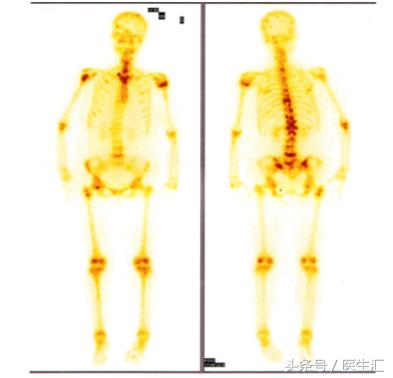

ECT(2015-6-11):全身多发性骨代谢异常活跃,考虑肿瘤广

泛骨转移。

ECT(2015-6-11 外院):全身多发性骨代谢异常活跃,考虑肿瘤

广泛骨转移。